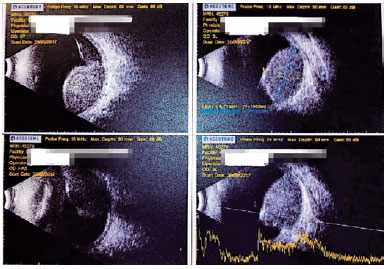

An 85-year-old Caucasian woman was referred in March 2017 for consultation after a fine-needle biopsy in an elevated choroidal tumor in the right eye (OD), by an outside ophthalmologist. The lesion was diagnosed following a complaint of 2-month unilateral progressive vision loss. Ocular magnetic resonance imaging and ultrasonography before the procedure demonstrated a single choroidal mass with associated serous retinal detachment (Figures 1 and 2), and fluorescein angiography showed a nasal choroidal mass (Figure 3).

In December 2018, she returned complaining of worsening vision in the OS, in which her BCVA was 20/50. Findings on slit-lamp examination and applanation tonometry measurements were within normal limits. A dilated fundus examination revealed an elevated macular mass. An ocular sonogram showed a choroidal mass with irregularly high internal reflectivity, with a basal diameter of 11 mm and thickness of 4 mm. Angiofluoresceinography identified a hyperfluorescent elevated macular mass. As the diagnosis was compatible with ocular metastasis, the family, and oncologist decided not to pursue any ocular intervention. The patient died 6 months after the diagnosis of metastasis in the second eye.